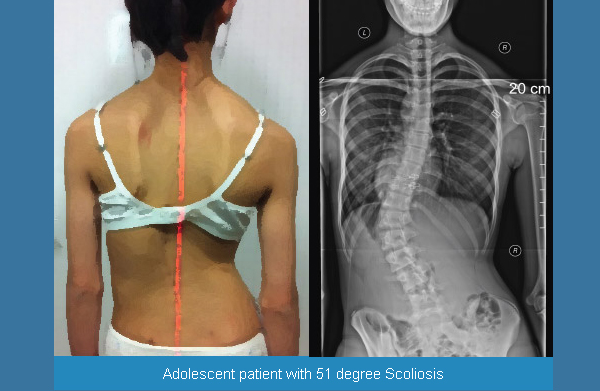

Искривление позвоночника: причины и последствия на снимках

Раздел: Визуальный дайджест